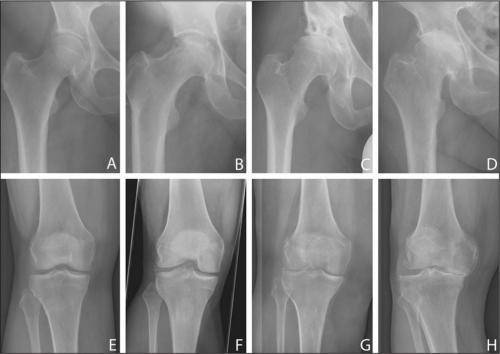

Показания и препараты для уколов в коленный сустав при артрозе

Если у человека заболевания суставов (артриты, артрозы), он испытывает немало мучений. Когда стандартные методы лечения не помогают, врач назначает уколы в коленный сустав, чтобы усилить эффект лекарственного препарата или же снять сильную боль.

Показания к уколам в колено

- при артрите;

- от артроза;

- при остеоартрозе;

- при гонартрозе коленного сустава;

- при бурситах;

- синовитах;

- тендинитах и других суставных заболеваниях.